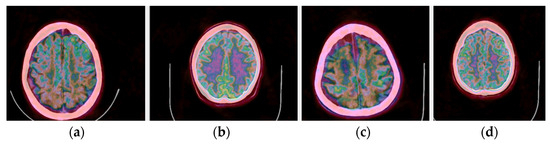

3.1. CIT Application

3.2. Colormap Folding Application